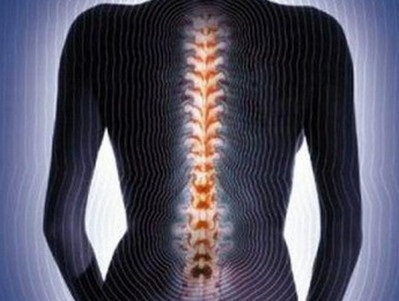

Mindig figyelje a testedet. Nagyon fontos, hogy ne hagyja ki azt a pillanatot, amikor az ízületi fájdalom, amelynek ciklikussága és az éjszakai pihenés után halványodik, nem az egyszerű fáradtság következménye. A vénás vér torlódásával a fájdalomban rémálom éppen éjszaka. Az osteoarthrosis először deformál egy kötést, majd a következő láncreakciót, amely nagyobb terhelést eredményez. Gyakran hallja, hogy ezt nevezik sóleválasztásnak. Ennek a kellemetlen betegségnek a legkedvesebb áldozatai a térdízületek, a nyaki és ágyéki gerinc, a boka, a vállak és a kefék. A gerinc osteoarthritis az osteochondrosis.

Példák az intervertebrális lemezek betegségeire